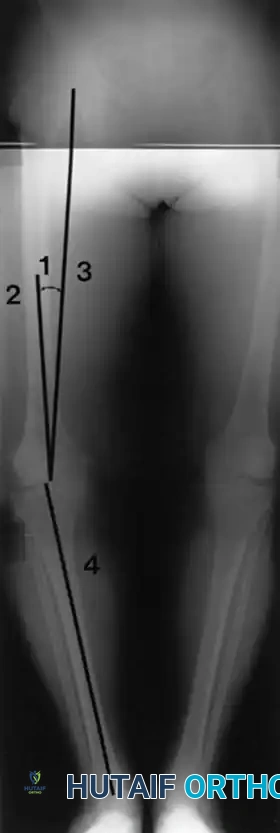

Fig. 6-26 Anatomical and mechanical axes of femur and tibia are determined independently on preoperative long-leg radiographs, with the goal of centering postoperative mechanical axis of limb within center of prosthetic knee. 1, Angle between anatomical (2) and mechanical (3) axes of femur. 4, Mechanical axis of tibia (see text).

The long-leg film allows the surgeon to calculate the angle between the anatomical axis of the femur (the intramedullary canal) and the mechanical axis of the femur (a line drawn from the center of the femoral head to the center of the knee). This angle, typically between 5 and 7 degrees, dictates the valgus cut angle set on the distal femoral cutting block. Furthermore, the long-leg film is vital for identifying significant diaphyseal bowing of the tibia or femur, which may preclude the use of standard intramedullary alignment guides and necessitate extramedullary referencing or computer-assisted navigation.